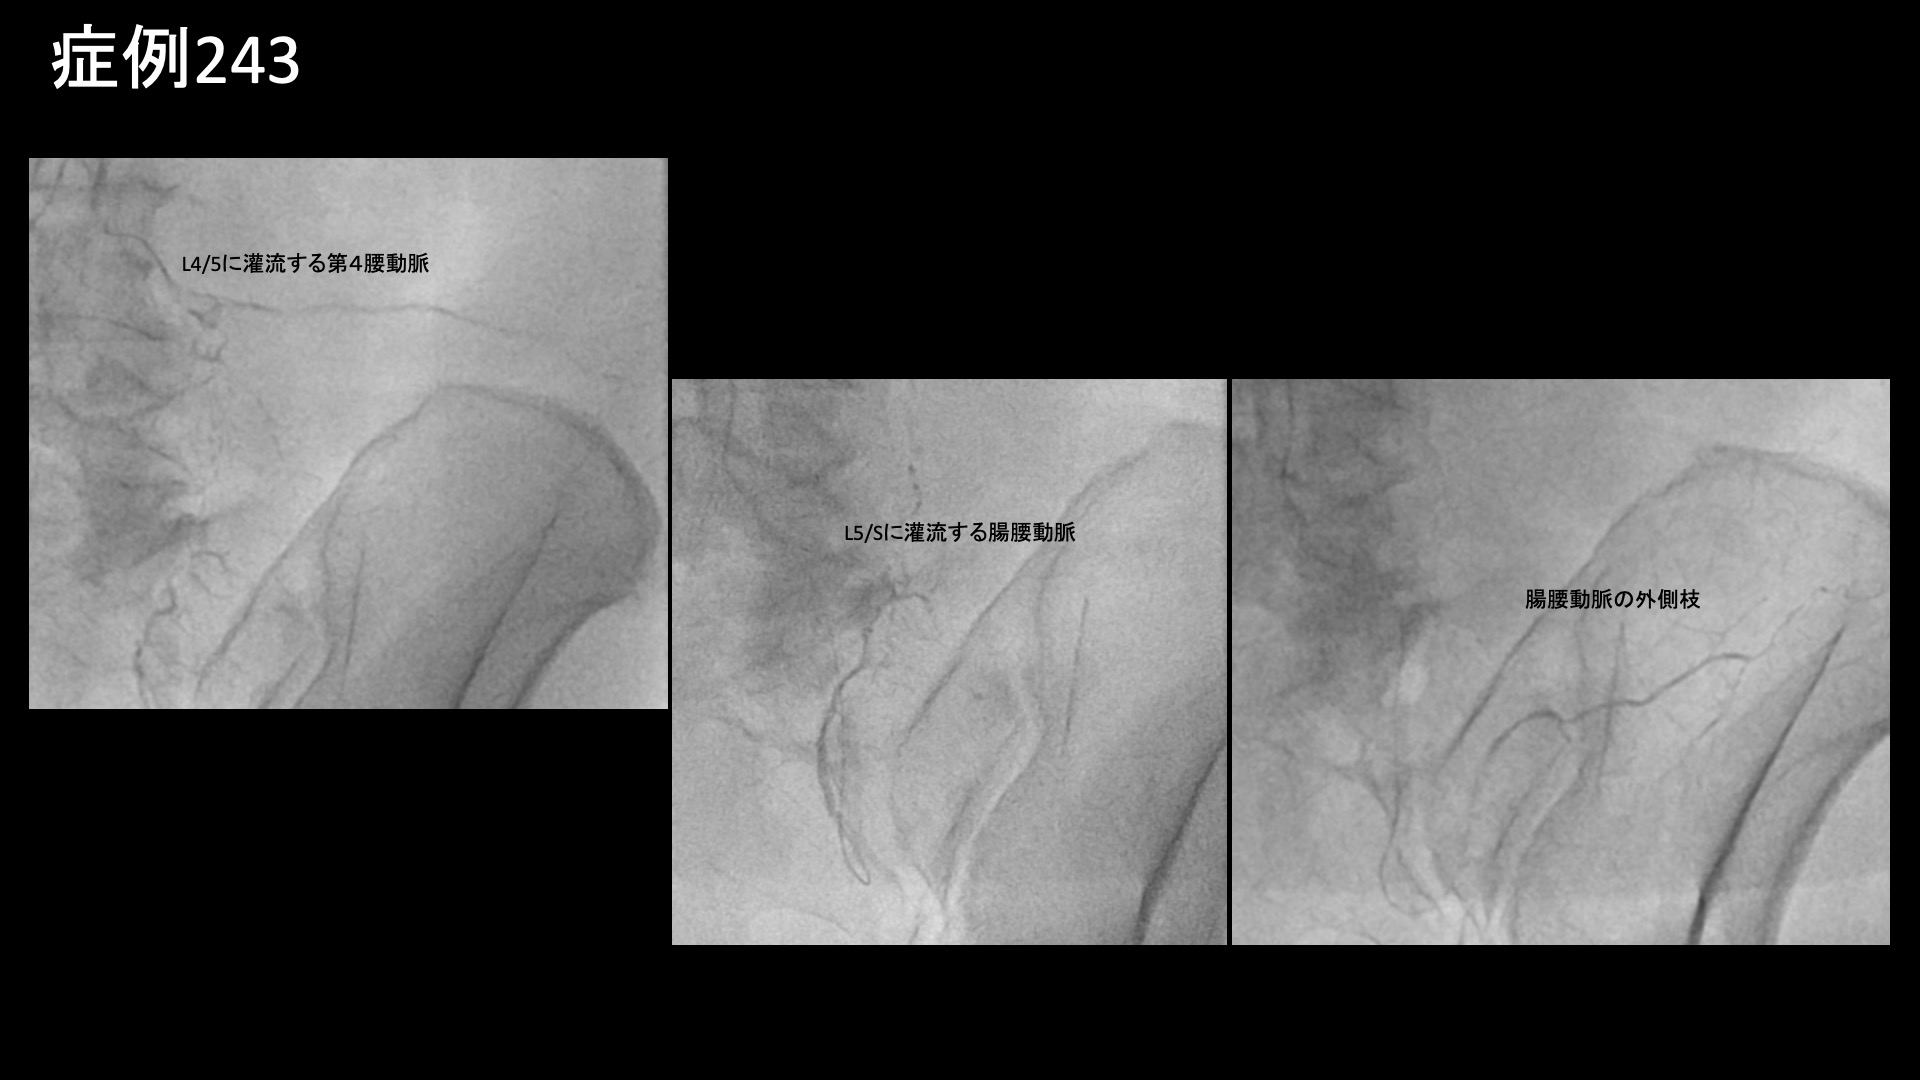

椎間孔狭窄部周囲を網羅するように、第4腰動脈や腸腰動脈の治療を行ったほか、その他の筋肉枝や仙腸関節周囲や股関節周囲に至るまで坐骨神経経路を含めて広く治療を行いました。第4腰動脈や腸腰動脈では特に再現痛を認めました。